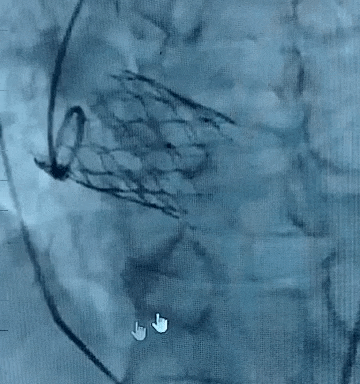

CASE 2为纯反流三叶瓣,敞口流出道、左窦异常扩大、STJ及升主略微增宽,瓣环直径24.1mm。术中应用自膨短瓣完成窦部增宽单一瓣环平面锚定,小oversize选择TAVTF 27mm瓣膜,术中瓣膜释放稳定性极佳,实现零张力无位移释放,脱钩后造影无窦近零位,左冠窦约瓣下3mm,多角度评估瓣膜位置与形态良好,术后无反流和位移。

CASE 2:脱钩后造影